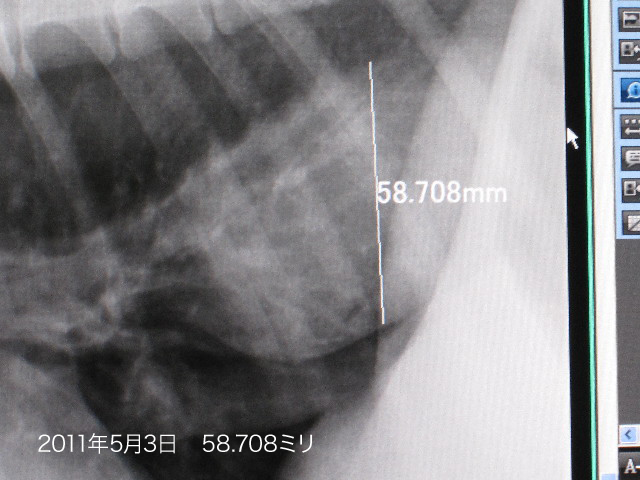

4ケ月ぶりにレントゲンを撮ったら

●哀しいかなべべちゃんのnQちゃんの直径が6.861ミリも大きくなってしまっていました。。。。

(1月4日は51.847ミリ/5月3日は58.708ミリ)

色々頑張っているのに、Qちゃんは少しずつ大きくなってしまっているのね(哀)

いつか手術も視野にいれないとならないかも?しれないけれど、今はまだ吐出しないのでこのまま様子をみましょうってことに。

Qちゃんが大きくなっていたのはショックだったけど(こんな時だから被爆を少しでもさけるためにあえてレントゲンを撮らないでいたの)、弱気になんてなってないよ!